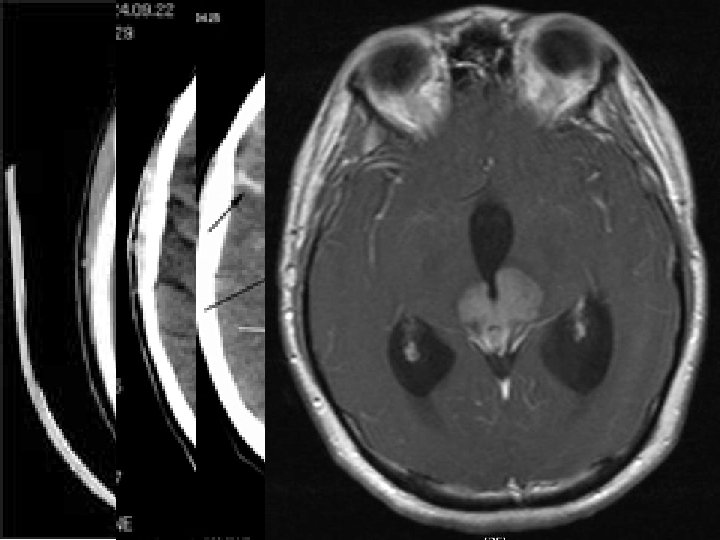

Šišinka • za horním zadním koncem III. komory • součást epitalamu • rudimentární endokrinní žláza s tlumivým účinkem na činnost pohlavních žláz pubertas praecox • dorzálně vybíhá nad mozkový kmen (nad čtverohrbolí středního mozku) • melatonin změna hladiny během dne • acervulus cerebri (= vápenaté konkrementy u dospělých) – CT, MRI